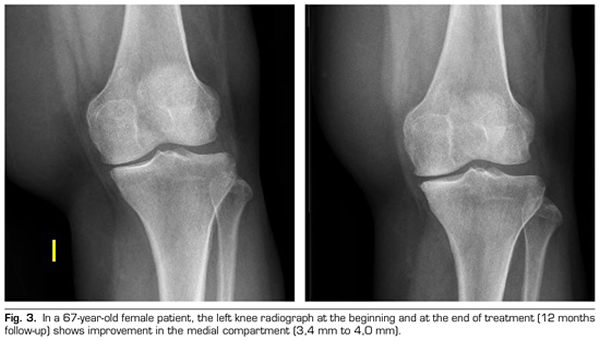

Radiological variables: In 53 patients analyzed radiologically (according to standardized protocol) at one year of follow-up after ozone treatment, the internal compartment increased significantly from 4.12 ± 1.41 mm to 4.4 ± 1.35 mm (p = 0.0008) and the external compartment increased from 6 ± 1.37 to 6.16 ± 1.4 mm (p = 0.0753).

Figure 3